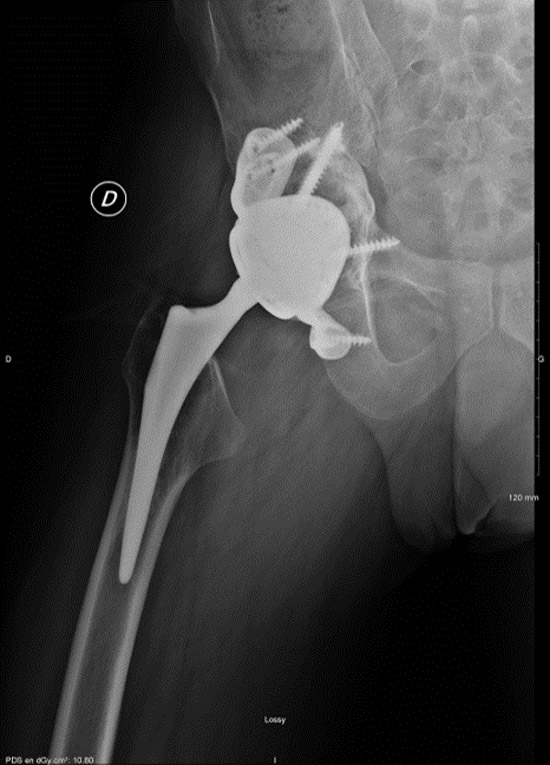

Postoperative imagery

> 2 years imagery

In this case, we decided to perform a scan-guided pre-operative puncture to rule out a septic cause. We then implanted a custom-made 3D implant (ADLER) to compensate for the bone defect and perform a unipolar revision of the acetabular side with a dual mobility cemented cup. We made this choice because the bone loss could not have been compensated for by an autograft and/or a support ring.